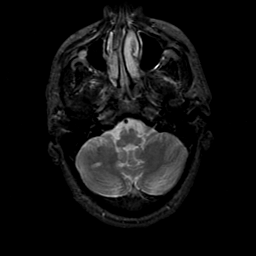

MR Study #21, November 3, 1991 -- Slice #9

[Home][Help][Clinical][Tour 1][Tour 2] Slice 9